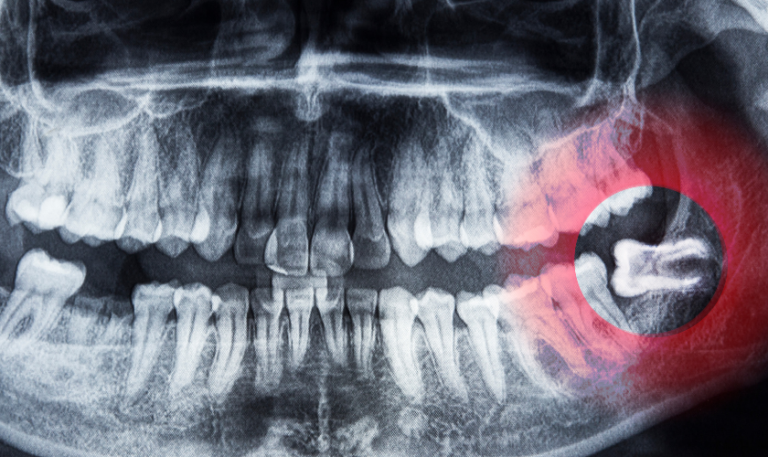

1. Consultation and Evaluation: A comprehensive assessment by a skilled San Antonio implant dentist to determine candidacy.

2. Surgical Placement: Titanium implants are precisely placed into the jawbone, providing a secure foundation for the restoration.

3. Healing and Osseointegration: The jawbone fuses with the implants during a healing period, ensuring stability.